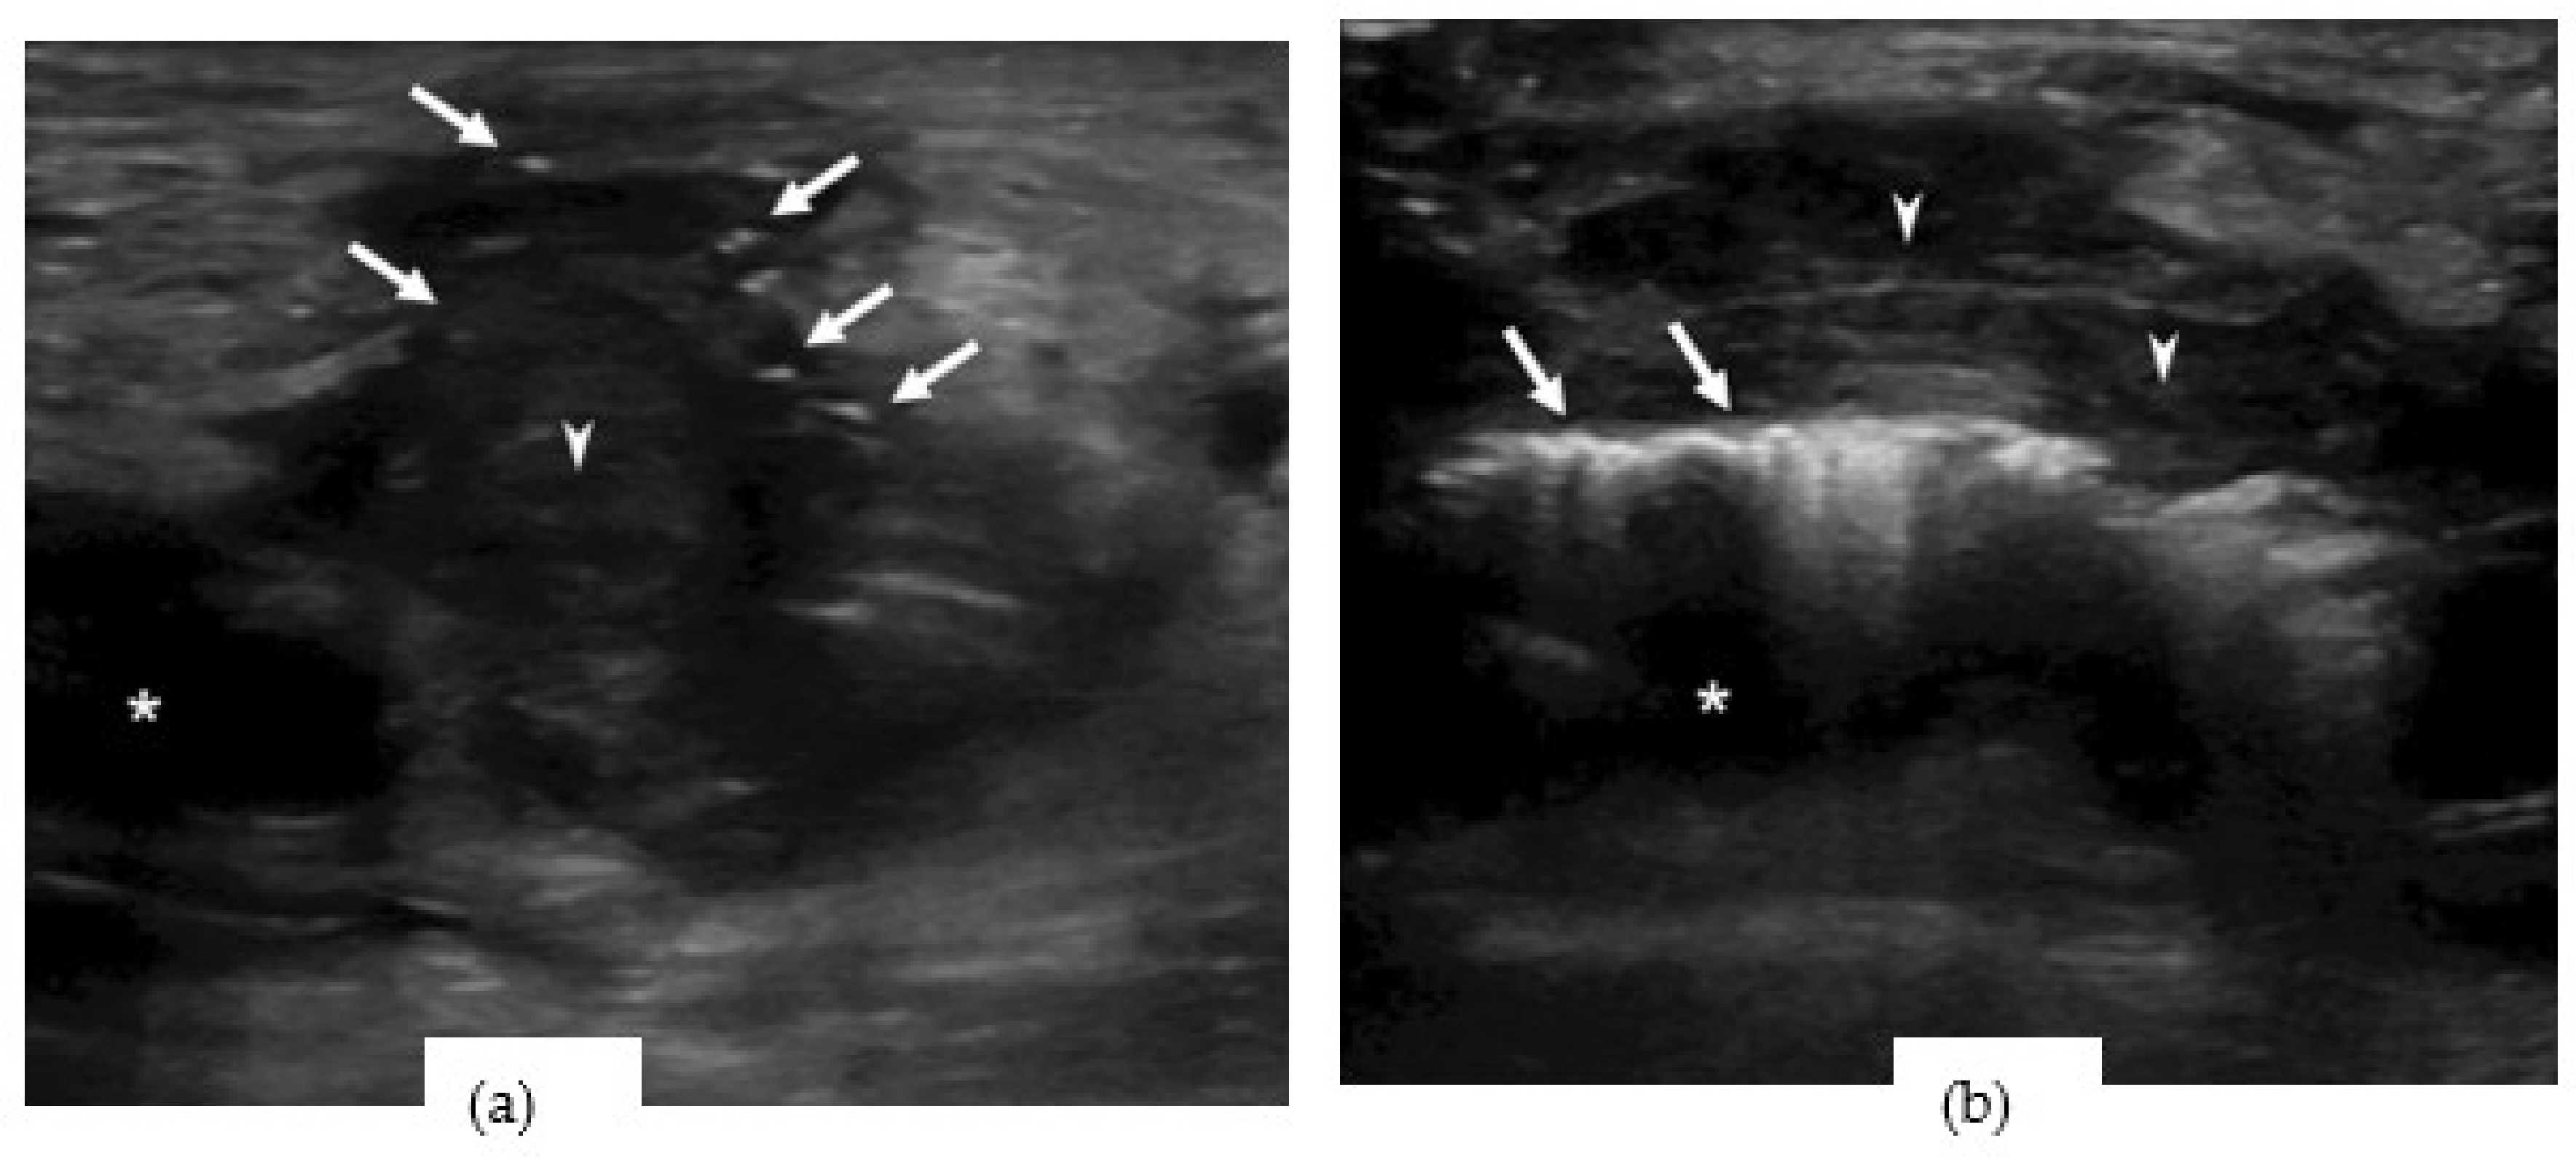

A point-of-care ultrasound (POCUS) revealed a large hypoechoic mass with a dirty shadow on the right groin area (Figure 1a). Dirty shadowing is thought to be produced by sound-reflecting materials such as subcutaneous free air [1]. An echogenic rim with dirty posterior shadowing along the pulsatile femoral artery was found next to the hematoma (Figure 1b). A video recording of the soft tissue echogram (Video S1 and Video S2) was obtained.

Figure 1. Point-of-care ultrasound revealed (a) A hypoechoic mass (arrowhead) surrounding with a dirty shadow (arrows) around the femoral artery (asterisk). (b) A hypoechoic mass (arrowhead) and an echogenic rim with dirty posterior shadowing (arrows) along the femoral artery (asterisk).